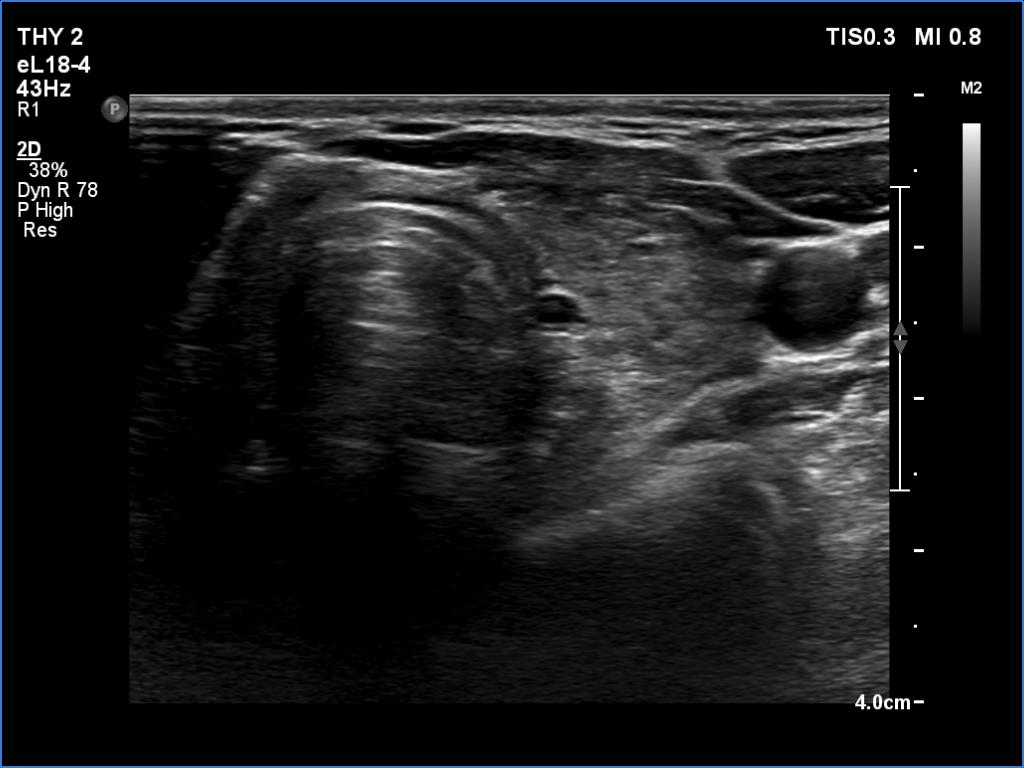

Ultrasonography. The thyroid was hypoechoic and presented several more hypoechoic and echonormal islets corresponding to the underlying thyroiditis. There was a mixed, dominantly cystic mass dorsal to the lower two-third of the right lobe. The lesion has echonormal solid part and showed intracystic echogenic figures.